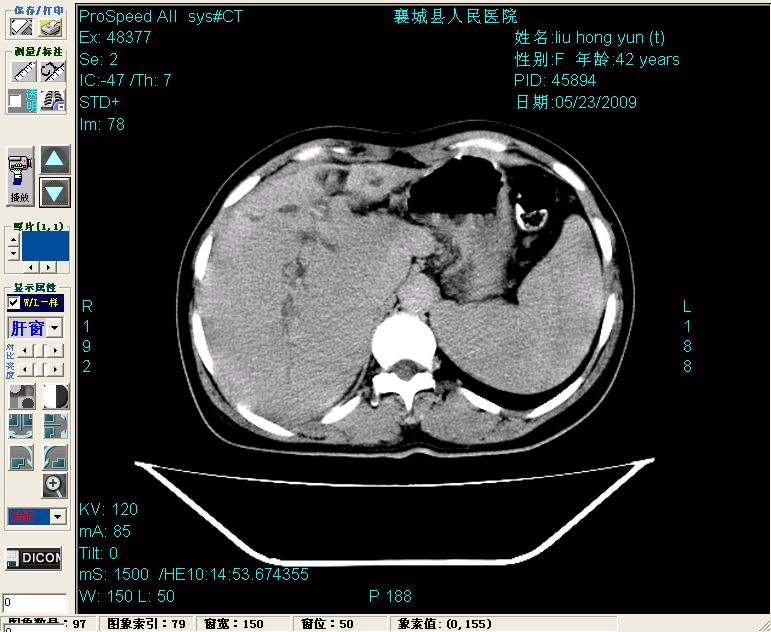

增强:

增强动脉期前述低密度区轻度早其强化,门脉期强化程度显著增高,延期扫描强化程度下降,但仍为相对高密度影

胰头部见结节状高密度影,其前方略可分辨扩强胆部管,平扫到增强始终有,但现在尚难与胃肠造影剂鉴别.